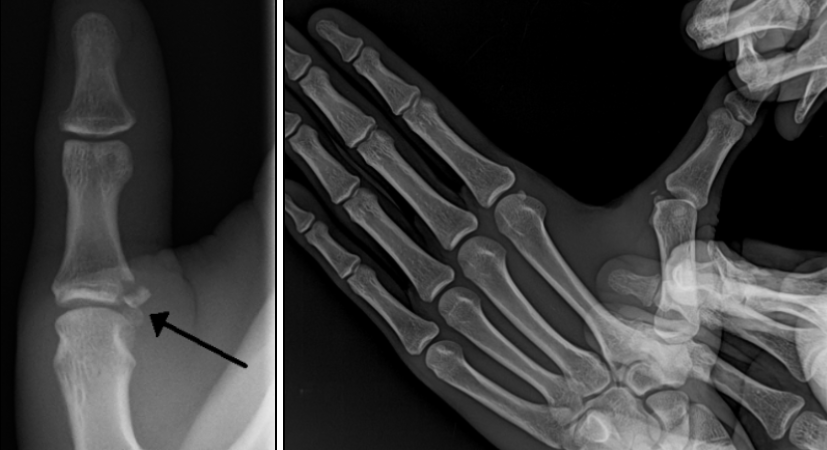

X-ray로 뼈 골절 확인, MRI나 초음파로 인대 손상 정도 평가.

x-ray상 인대파열이 되면서 동반된 견열골절 및 스트레스시 이완(laxity)이 두드러짐